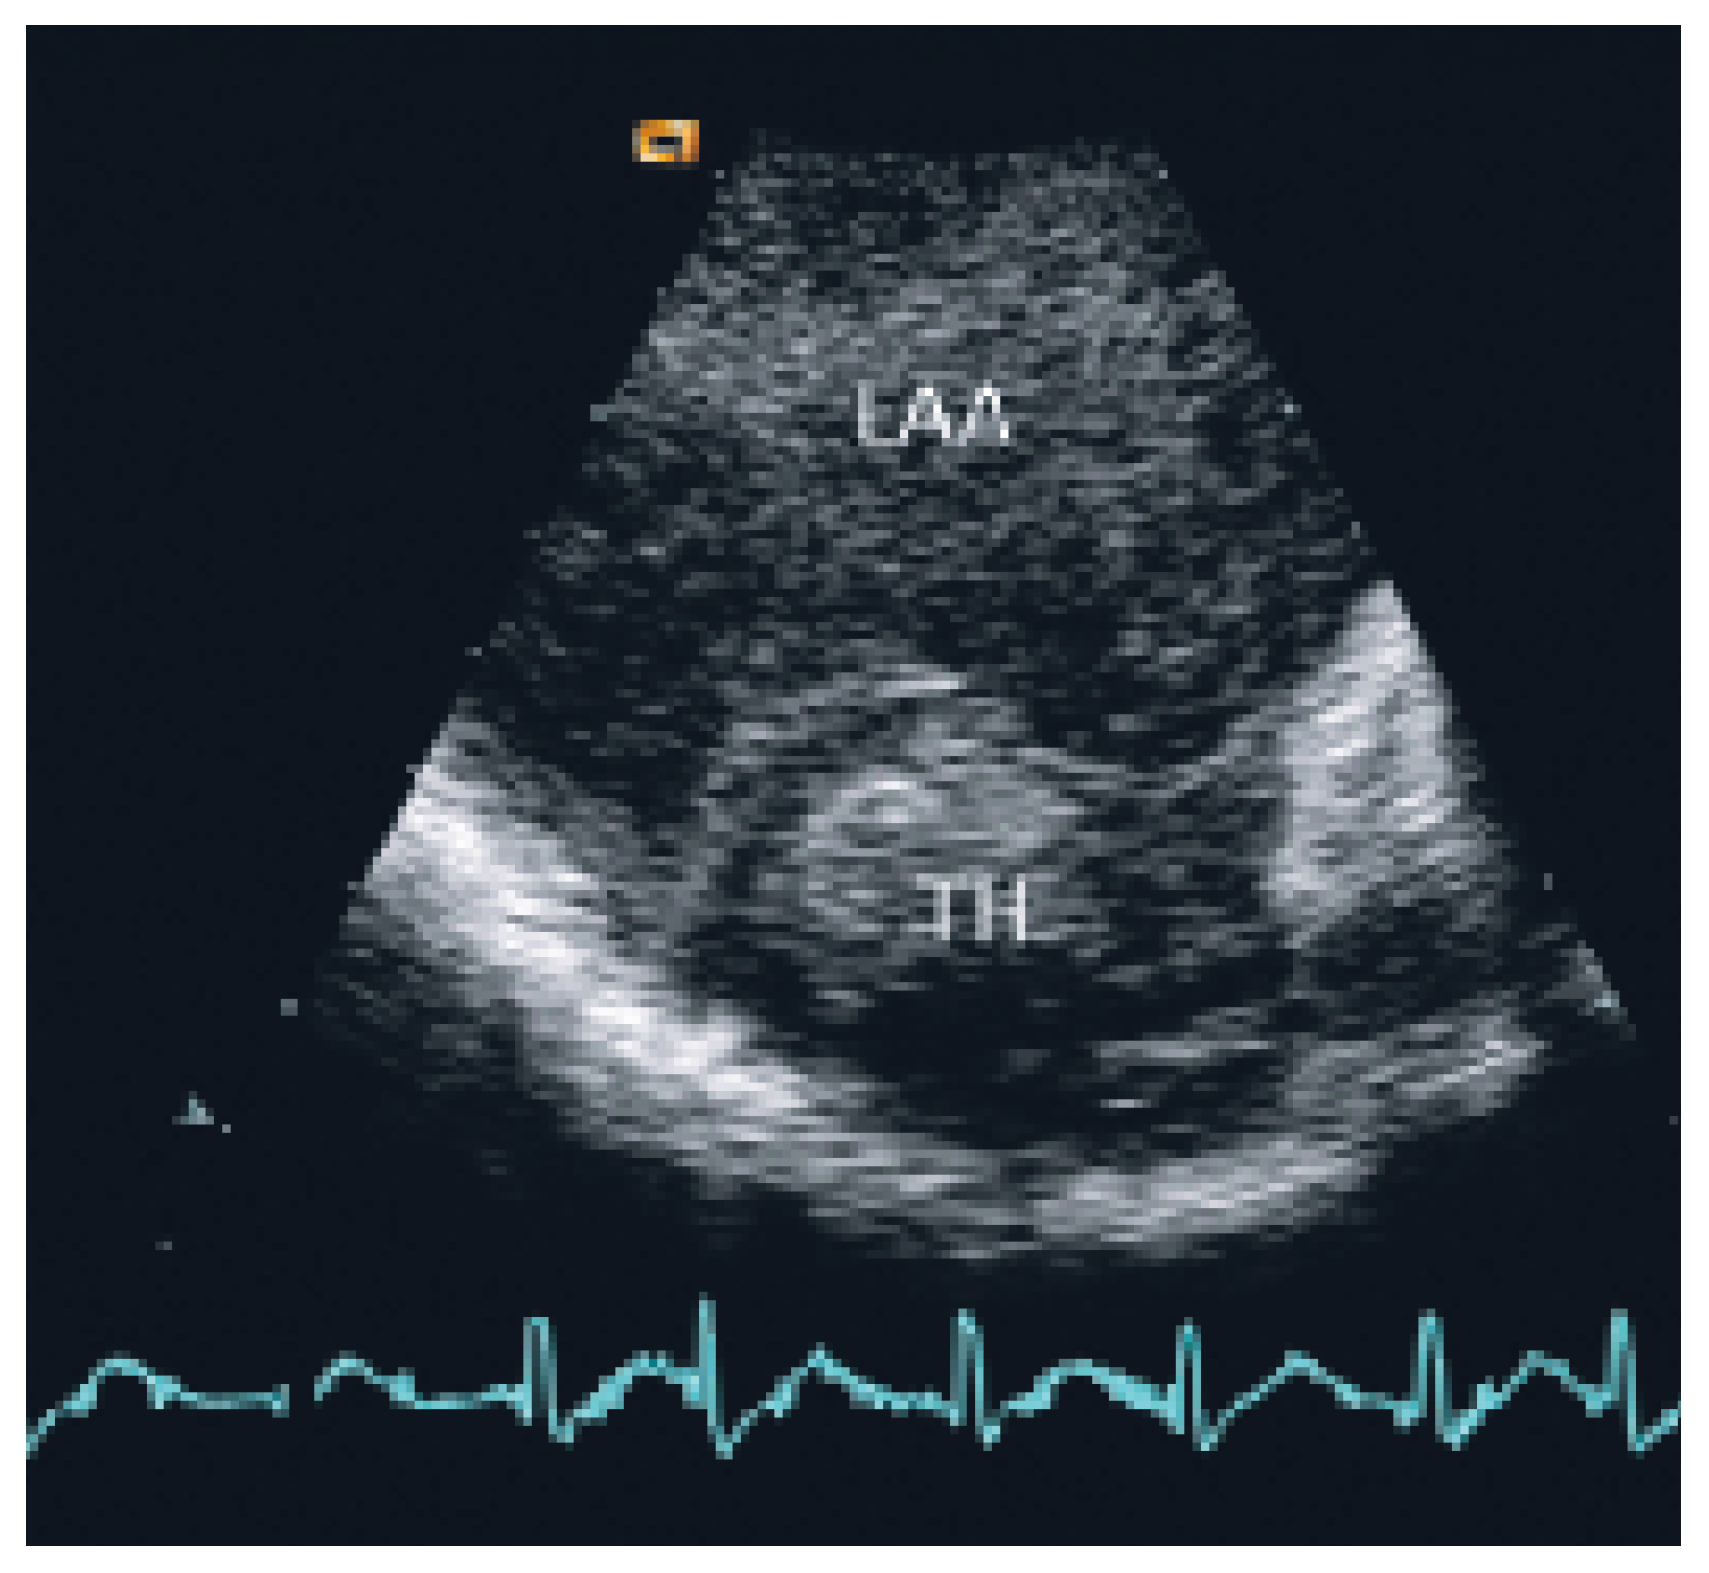

The patient was transferred to the intermediary care unit with the clinical diagnosis of subacute transmural anterior myocardial infarction. TTE showed a giant left atrium (9 cm × 12 cm × 9 cm; 509 cm3) and a large aneurysm of the atrial septum with compression of the right atrium (Figure 1) also as an apical scar, compatible with subacute myocardial infarction (Figure 1).

As cited in Hurst’s memories [1] “… giant left atrium is defined as one that touches the right lateral side of the chest wall. The condition is caused by rheumatic mitral valve disease and atrial fibrillation is always present …”. This case illustrates the pivotal role of echocardiography in defining and quantifying this pathology and the associated thromboembolic risk. TTE and particularly TEE allowed to assess the magnitude of the giant left atrium (Figure 1), the presence of spontaneous contrast and intracardiac thrombus (Figure 2 and 3), the presence of normal functioning of the mechanical valve prosthesis, and the occurrence of a new apical dyskinesia compatible with the diagnosis of acute myocardial infarction [2].

Figure 1. Transthoracic echocardiography shows a giant left atrium with a severe aneurysm of interatrial septum with displacement to the right. LA = left atrium; LV = left ventricle; RA = right atrium; RV = right ventricle.